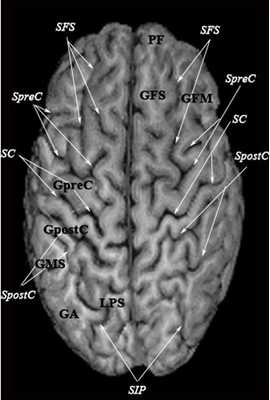

МРТ головного мозга. Объемное представление поверхности коры. Цветовая обработка изображения.

Список сокращений

Борозды

Междолевые и срединные

SC - центральная борозда

FS - Сильвиева щель (латеральная борозда)

FSasc - восходящая ветвь Сильвиевой щели

FShor - поперечная борозда Сильвиевой щели

SPO - теменно-затылочная борозда

STO - височно-затылочная борозда

SCasc - восходящая ветвь поясной борозды

SsubP - подтеменная борозда

SCing - поясная борозда

SCirc - круговая борозда (островка)

SpreC - предцентральная борозда

SparaC - околоцентральная борозда

SFS - верхняя лобная борозда

FFM - лобно-краевая щель

SOrbL - латеральная глазничная борозда

SOrbT - поперечная глазничная борозда

SOrbM - медиальная глазничная борозда

SsOrb - подглазничная борозда

SCM - мозолисто-краевая борозда

SpostC - постцентральная борозда

SIP - внутритеменная борозда

STS - верхняя височная борозда

STT - поперечная височная борозда

SCirc - круговая борозда

SCalc - шпорная борозда

SOL - латеральная затылочная борозда

SOT - поперечная затылочная борозда

SOA - передняя затылочная борозда

Извилины и доли

PF - лобный полюс

GFS - верхняя лобная извилина

GFM - средняя лобная извилина

GpreC - предцентральная извилина

GpostC - постцентральная извилина

GMS - надкраевая извилина

GCing - поясная извилина

GOrb - глазничная извилина

GA - угловая извилина

LPC - парацентральная долька

LPI - нижняя теменная долька

LPS - верхняя теменная долька

PO - затылочный полюс

GR - прямая извилина

PT - полюс височной доли